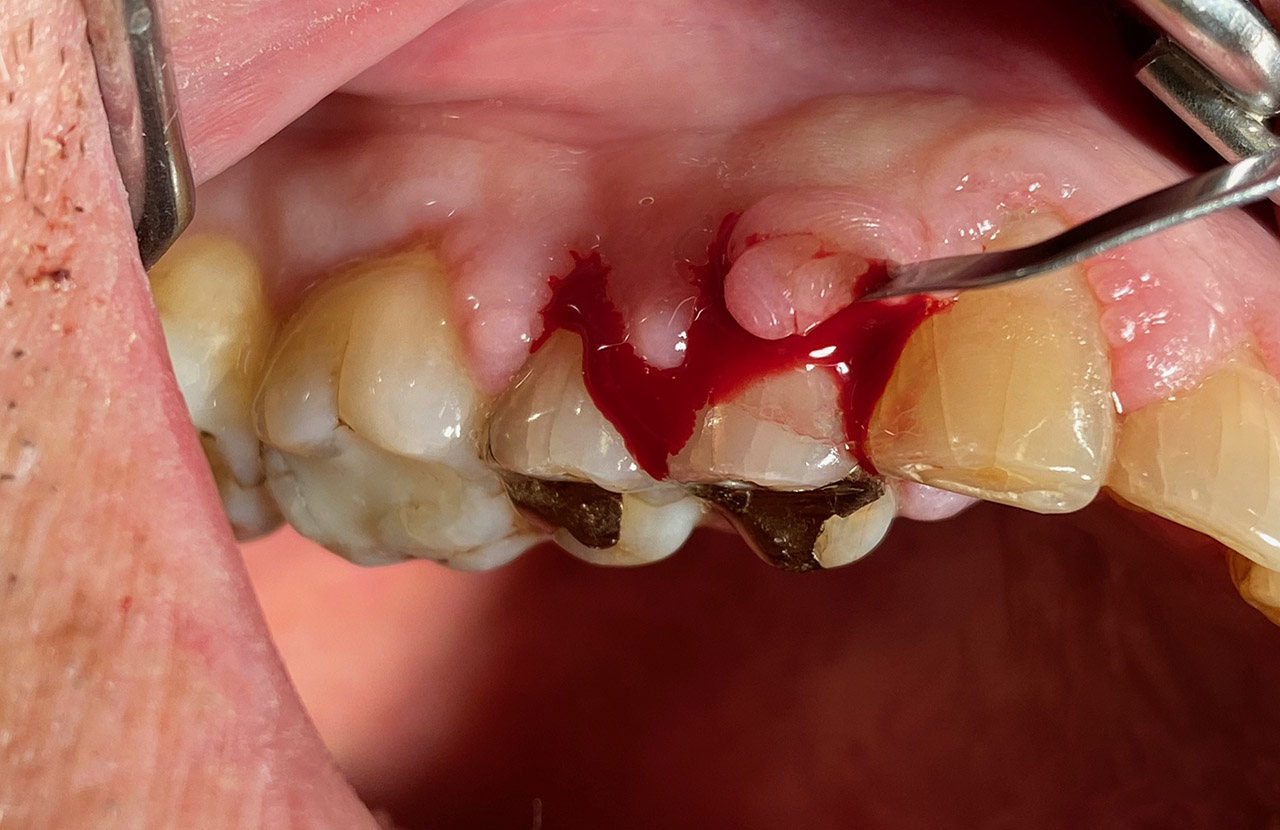

Parodontologie/Gingivahyperplasie:

Diagnose: Gingivahyperplasie durch Medikamente (Blutdrucksenker), unzureichende/nicht mehr mögliche Mundhygiene und überstehende Füllungen.

Therapie: Gingivektomie und anfinieren der Füllungen. Letztes Foto 1 Woche postOP.